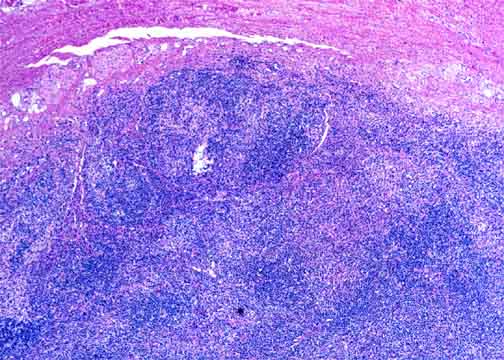

Peripheral T-Cell Lymphomas: Example 1

This is a large cell PTCL that partially replaced the lymph node. The case is unusual for the banded or mottled pattern seen here at low power. A thickened capsule is at the top. |

At medium power the bands are evidently composed of stripes of small lymphocytes (which may or may not be part of the lymphoma), stripes of large cells with clear cytoplasm, and stripes of pink-tinged necrosis with neutrophils. While this pattern is unusual and visually arresting, it does not have any significance beyond that of its constituent cells. |